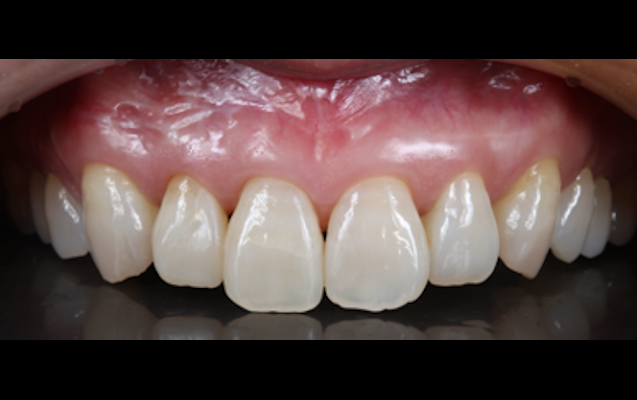

(実際の症例)

セラミッククラウンはご本人の歯を土台にしながら審美面を大きく改善でき、また噛み合わせや歯並びの矯正なども合わせて対応できることが特徴です。

当院では患者様一人ひとりに向き合った精密検査・診断を通してお口全体のバランスを整え、機能的で長持ちする審美治療としてセラミッククラウンをお作りしています。